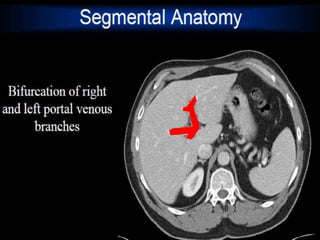

CT cross sectional anatomy.